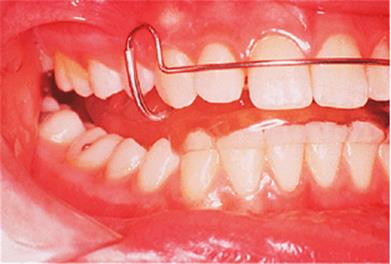

Before discussing functional appliances in detail, Fig. 18.1 gives an overview of this type of functional appliance in clinical use. This patient has a Class II division 1 malocclusion of the type for which functional appliances are very suitable, and for which they have been used for many years.

There are a number of important features to note which will be discussed further later in the chapter. First, the patient is still growing and the signs are that her pattern of facial growth is likely to be favourable. Although the skeletal pattern is Class II, the vertical relationships are close to average and the direction of mandibular growth is likely to be a mild forward rotation (see Chapter 4) which is favourable to the correction of a Class II malocclusion. Second, the soft tissue morphology is favourable despite the lips being incompetent, with the lower lip resting behind the upper incisors. The lower lip line is above the level of the upper incisal edges, and after the overjet has been reduced the lower lip will rest labially to the upper incisors, so helping to resist any tendency for relapse of the overjet. Third, the arches are well aligned — functional appliances have no mechanism for treating irregularities of alignment of the teeth.

Fig. 18.1. (a) This 12-year-old girl had a skeletal II facial pattern and average facial proportions. The lips were incompetent with the lower lip lying below the upper incisors at rest. (b), (c) She had a Class II division 1 malocclusion with an overjet of 10 mm, the overbite was increased and complete, and the molar relationship was Class II on both sides. (d), (e) The upper and lower arches were well aligned. (f) A functional appliance (an activator) was fitted. (g) The corrected occlusion with Class I incisor and molar relationships. (h) The patient's facial profile at the end of treatment.